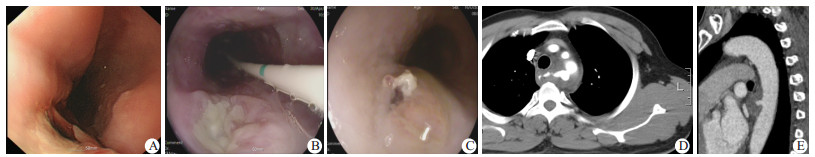

| A:病例2术后引流后食管瘘口; B:支架取出时瘘口愈合情况; C:病例3食管瘘口; D:病例2胸部CTA; E:病例3胸部CTA 图 1 患者胃镜检查影像(A~C)和胸部CTA结果(D~E) |

病例2:患者男性,52岁,入院前8 d进食鱼后出现咽喉部疼痛,行食管造影检查未见明显钩挂现象,胸正侧位片未见明显异常,行喉镜检查未见明显异物。4 d前患者出现发热,查胸部增强CT示后纵隔血肿,考虑食管异物所致食管穿孔并致主动脉破裂,行主动脉覆膜支架隔绝术,并行电视辅助胸腔镜手术(video-assisted thoracic surgery, VATS辅助下胸腔探查+纵隔感染清创引流+胃镜引导下引流管置入,术中胃镜示距门齿24 cm左右食管前壁有一溃疡,直径大小约0.5 cm,表面可见灰白色坏死物质及少量暗红色血凝块,未见瘘口,未见渗血及喷血,周围黏膜肿胀。术后予以亚胺培南西司他汀联合万古霉素抗感染治疗,脓液培养发现表皮葡萄球菌,苯唑西林耐药,万古霉素敏感,停用亚胺培南西司他汀。术后6 d引流管无脓液引流出,进一步行胃镜下食管覆膜支架置入+空肠营养管置管术,进镜见距门齿25 cm 8点钟方向可见一食管纵隔瘘口,大小约0.8 cm(图 1A),置入支架将瘘口完全覆盖(支架上口固定一丝线,并将丝线固定在口腔,防止支架脱落)。术后20 d后口服造影剂食管主动脉弓水平可见造影剂溢出,隔日取出支架,进镜见距门齿25 cm,见0.5 cm×1.0 cm白色糜烂性病灶(图 1B),原支架上下口处可见片状糜。术后28 d食管碘海醇造影,吞服造影剂后,食管未见造影剂溢出。患者拔出空肠营养管,经口进食,治愈出院,继续服用利奈唑胺5 d。

病例3:患者男性,46岁,入院前1周出现解柏油样黑便,3 d后自行转黄,曾有胸闷不适,无明显胸痛,15 h前呕血数次约1 000 mL,血红蛋白50 g/L,胃镜示食管中段可见一处隆起病灶,约0.6 cm×0.8 cm大小,表面欠光滑,可见一处破口,内可见血痂覆着(图 1C)。进一步胸部CTA:胸降主动脉破裂伴假性动脉瘤、纵隔血肿形成(图 1E)。当晚行主动脉覆膜支架隔绝术,术后放置空肠营养管,哌拉西林他唑巴联合万古霉素抗感染治疗,2周后复查胃镜观察全食管未见明显糜烂及溃疡,停抗感染治疗,拔出空肠营养管,经口进食,治愈出院。